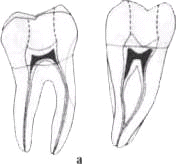

Средняя длина первых моляров 22 мм (20-24 мм). Как правило,

они имеют 2 корня (97,8 %), иногда 3 корня (2,2 %) с изгибом у нижней трети

(рис. 4-23).

Одиночный дистальный канал овальной формы и хорошо проходим.

В 38 % случаев в нем встречается 2 канала. В мезиальном корне 2 канала, но в

40-45 % случаев они открываются одним отверстием.

Полость зуба больших размеров в мезиальном направлении и

смещена в мезиально-щечном направлении, вследствие чего устья медиального корня

часто не раскрываются (до 78 %). Дно полости слегка выпуклое и располагается на

уровне шейки зуба. Устья каналов образуют почти равнобедренный треугольник с

вершиной у дистального корня, хотя полость зуба имеет форму закругленного

четырехугольника. Мезиальные каналы более узкие, особенно переднещечный, что

создает трудности для обработки, особенно у лиц пожилого возраста. Иногда

разветвления корневых каналов образуют густую сеть.

Рис. 4-23. Первый моляр нижней челюсти (схема). Выраженное

смещение полости зуба в щечно-медиальном направлении :

а - продольный разрез;

б - проекция полости зуба и устья канала на жевательную

поверхность коронки.